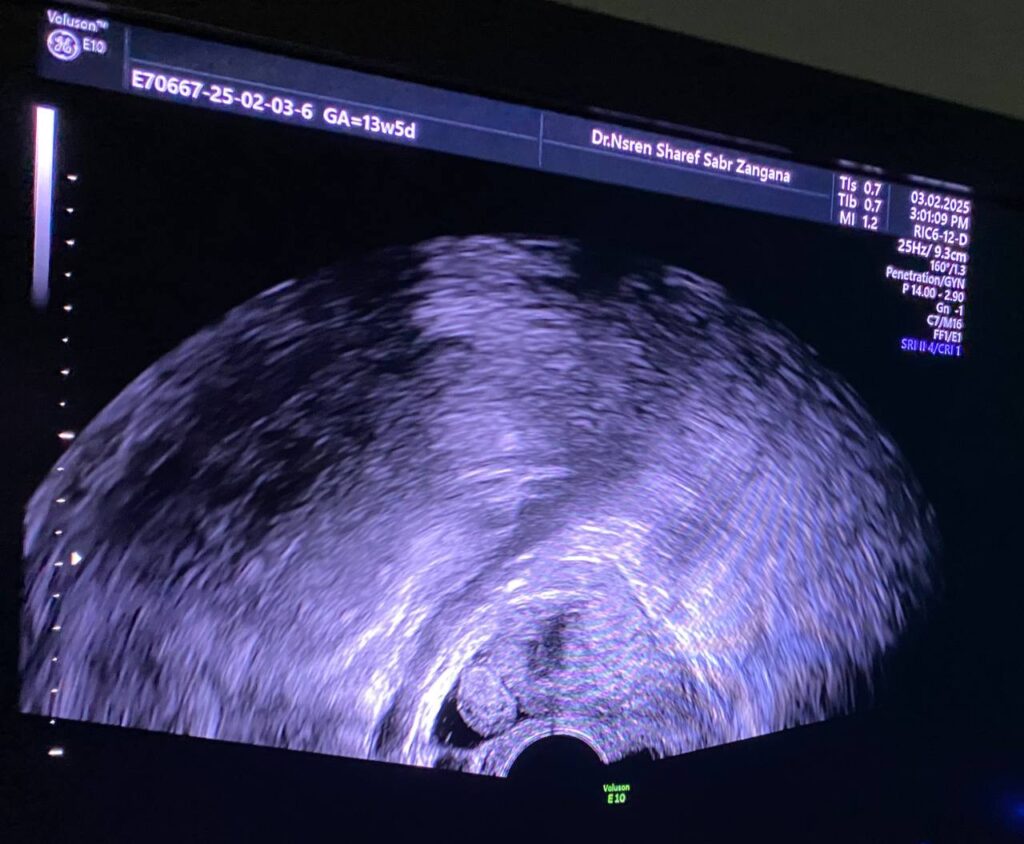

Right Ovarian pedicle Torsion U/S

Right ovarian avascular cystic mass size 75x41mm mostly physiological , with adjacent right adnexal mass size about 33x28mm , picture mostly of twisted ovarian pedicle? but ectopic pregnancy cannot be excluded , please for further study , also associated with small amount of free pelvic fluid <10ml mostly reactionary